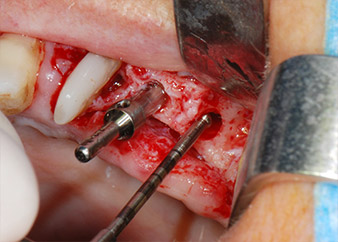

One month later, on the day of surgery, pain and inflammation at tooth 24 were minimal, but mobility of Miller class 2 was still present. After opening the flaps and cleaning the periapical and peri radicular infected tissue, the extent of the bone defect became obvious (Figs. 2 and 3).

At the buccal root, all vestibular and distal bone was missing. Attachment was essentially restricted to the palatal root, underlining the preliminary poor prognosis. Tooth 27 also showed a reduced horizontal attachment and a minimal apical rarefaction (cf. Fig. 1) without clinical symptoms.

total loss of bone and attachment

Fig. 2 and 3: After raising flaps, one month after endodontic revision and initiation of full-mouth periodontal therapy, the buccal root of tooth 24 showed a total loss of bone and attachment.

However, we maintained our initial plan to retain both teeth as temporary bridge abutments during the six-months osseointegration period of the implants. At reentry, the situation would have to be reassessed. First, in an attempt to manage the endo-perio problem, the remaining root surface was carefully debrided with piezoelectric equipment (Piezomed, W&H, used with the spatula-shaped insert S1, originally designed for erosion of the lateral sinus wall) (Fig. 4).